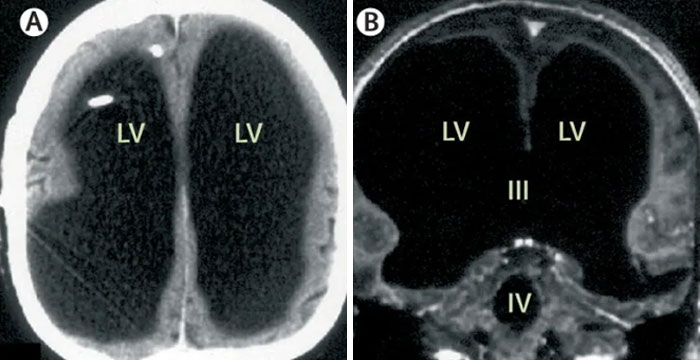

TIL of a man who was discovered to be unknowingly missing 90% of his brain, and was living a normal life.